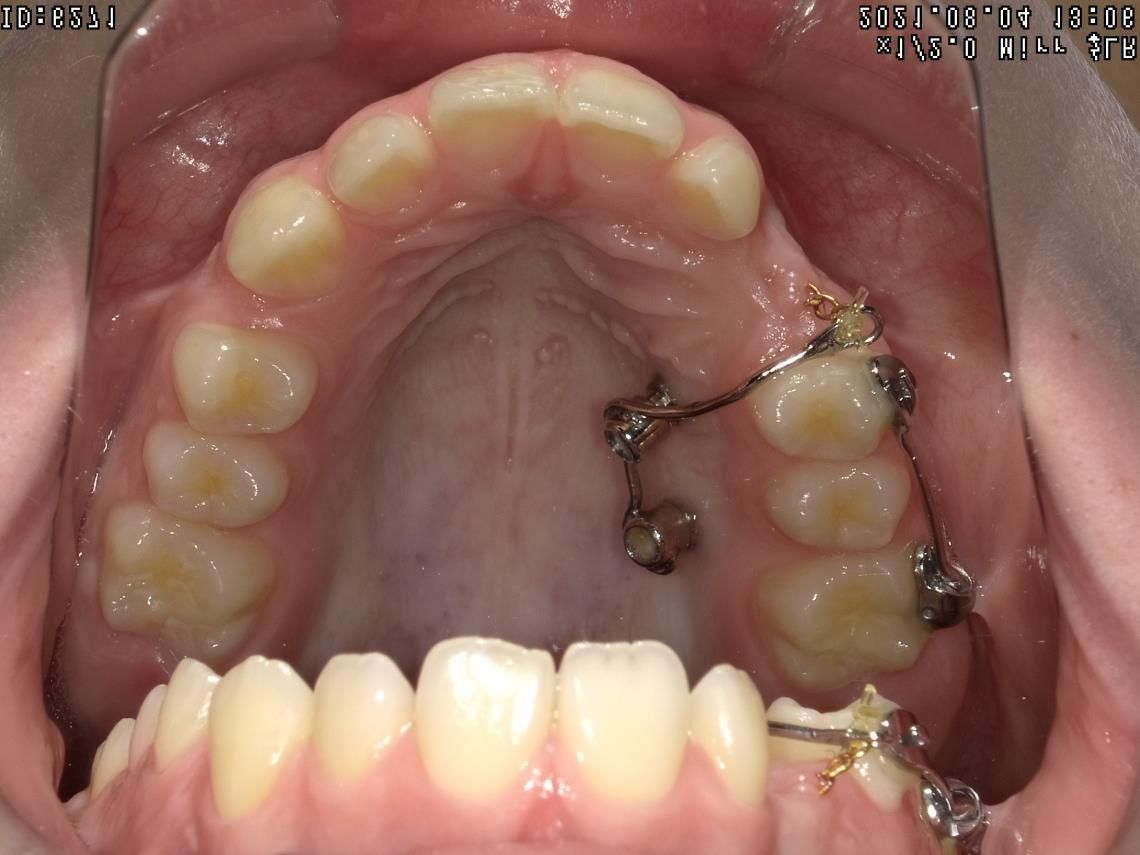

LES BAGUES

Cet appareil dentaire fixe est composé de brackets ou bagues, sortes de petits boutons en métal, en plastique ou en céramique, collés sur les dents et reliés par un fil. Il permet de déplacer les dents du patient dans la direction optimale, de les réaligner au fur et à mesure, de traiter des cas complexes de manque de place et des dents retenues ou dystopiques. Le traitement est moins tributaire de la coopération du patient.